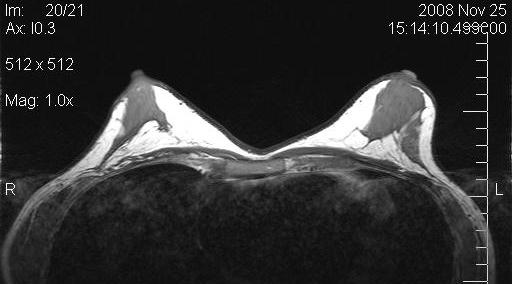

MRI investigations

Magnetic resonance imaging (MRI) of the breasts was performed in 5 patients preoperatively and 6 months postoperatively. The evaluation by MRI based volumetry gave inconsistent results, presumably due to the fact that volume (the implant) is first removed, and then added by fat grafting in one procedure. Also, the form of the preoperatively often very tight breasts changed dramatically. All MRI showed massive increase in fat tissue. No cysts were observerd.

Figure 10 [Fig. 10] and Figure 11 [Fig. 11] show the MRIs of a patient pre- and postoperatively.

Figure 10: Preoperative MRI of a patient with capsular contracture

Figure 11: Postoperative MRI of the same patient after implant removal and subsequent fat grafting